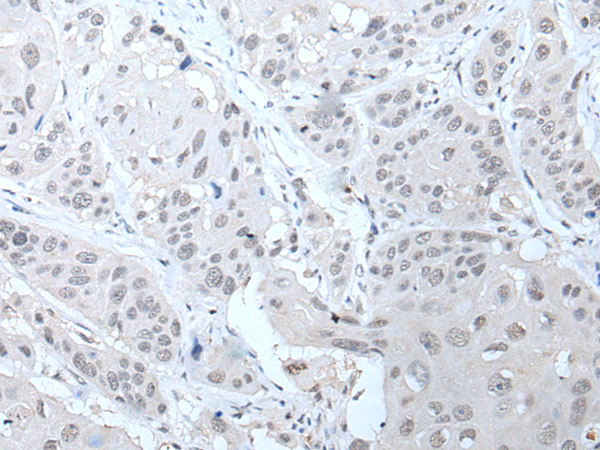

分类: 科研抗体货号: P12780别名: CT3.3; MAGE-B5应用: IHC反应种属: Human